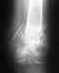

Косолидирующийся двухлодыжечный перелом правой голени со смещением наружной лодыжки. Получили отказ от операции.

Доброго времени суток. Моя мама получила травму ног 11 марта. Из травматолгии она была направлена на операцию, но ей дважды отказали в госпитализации: сначала из-за мокнущих ран, спустя 3,5 недели (кода раны зажили) из-за того, что перелом уже старый и кости начали срастаться, хоть и со смещением. Сегодня диагноз:Косолидирующийся двухлодыжечный перелом правой голени со смещением наружной лодыжки. Правая нога в циркулярном гипсе. Вопросы: - Так нужна ли операция? Если да, то где ее можно сделать (в Екатеринбурге)? - Как будет работать нога после неправильно сросшегося перелома, голеностопный и коленный суставы?